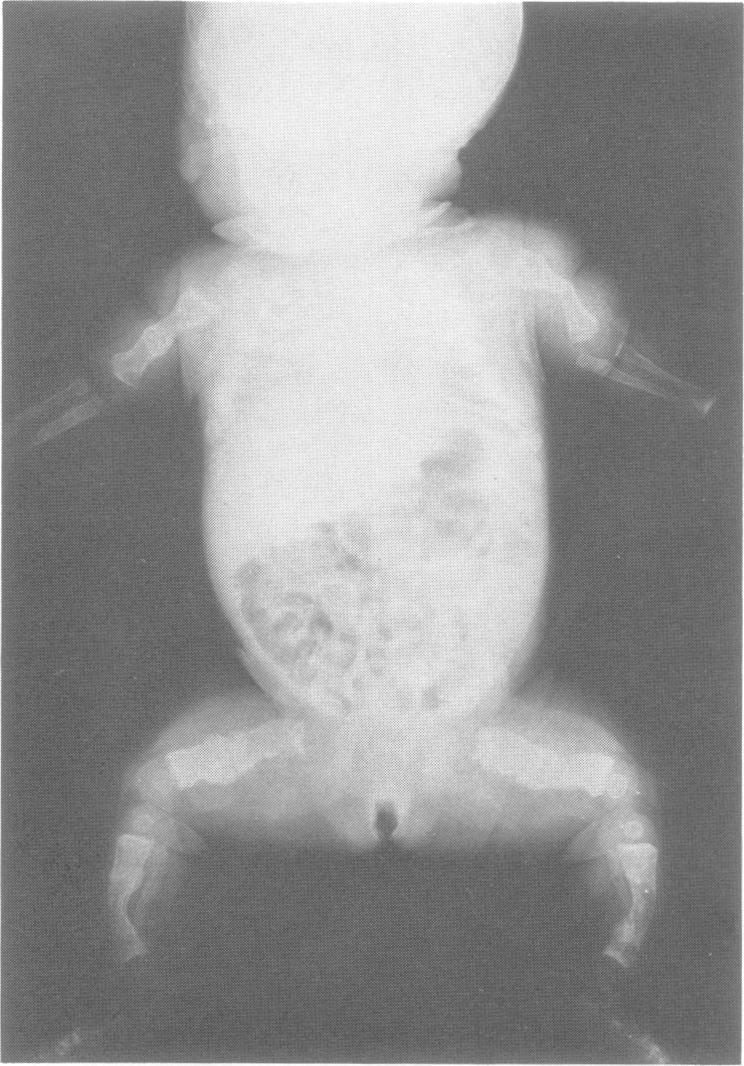

A study was carried out in the United Kingdom of patients with severe osteogenesis imperfecta (OI), born with fractures to normal parents, in order to determine recurrence risks. A total of 105 cases from 98 families survived the perinatal period and 60 cases from 57 families were stillborn or died during the first week of life. The majority of the perinatal survivors correspond to the overlapping group of Sillence type III and sporadic type IV OI. In 40 of these, the radiograph at birth was available and in 37 it showed a characteristic appearance similar to that described previously for type III OI. The other three cases had radiological type IIB OI at birth and died before 26 months of age. The patients with perinatally lethal OI were subdivided on radiological appearance into Sillence type IIA (30 cases, described in the previous paper), type IIB (12 cases from 11 families), and type IIC (three cases from three families), and in five cases from three families the radiological appearance was the same as that of the 37 perinatal survivors described above. Ten cases from 10 families were not classified because their radiographs were unavailable. To analyse the empirical recurrence risks, patients were grouped according to radiological appearance at birth. Those with a type III-like pattern numbered 42 cases and they were grouped with the other cases of severe deforming OI who survived the perinatal period, for whom no x ray at birth was available, making a total of 107 cases. Taking one affected child per family as the proband, there were 98 probands. They had 146 sibs, of whom 10 were affected, giving an empirical recurrence risk of 6.9%. This is consistent with the disease arising as a new dominant mutation in about three quarters of families and as a recessive in about one quarter in this heterogeneous group. It is reasonable to give a recurrence risk of up to 25% in cases with parental consanguinity and a risk of 4.4% in cases with unrelated parents. Fifteen patients (14 probands) with Sillence type IIB OI had 13 sibs, one affected, giving an empirical recurrence risk of 7.7%. The parents were consanguineous in three families and the evidence for autosomal recessive inheritance for the majority in this group is probably stronger. The three patients with type IIC OI had three healthy sibs and the 10 unclassifiable perinatally lethal cases had 22 sibs, all normal. The radiological appearance at birth predicts prognosis to some extent; essentially, the better the bone morphology and mineralisation the longer the survival.

在英国对患有严重成骨不全症(OI)的患者进行了一项研究,这些患者出生时父母正常却伴有骨折,目的是确定复发风险。来自98个家庭的105例患者度过了围产期,来自57个家庭的60例患者在出生后第一周内死产或死亡。围产期存活的大多数患者属于Sillence III型和散发IV型OI的重叠组。其中40例患者出生时的X光片可用,37例显示出与先前描述的III型OI相似的特征性表现。另外3例患者出生时为IIB型OI,在26个月前死亡。围产期致死性OI患者根据X光表现分为Sillence IIA型(30例,在上一篇论文中描述)、IIB型(来自11个家庭的12例)和IIC型(来自3个家庭的3例),来自3个家庭的5例患者的X光表现与上述37例围产期存活者相同。来自10个家庭的10例患者未分类,因为他们的X光片不可用。为了分析经验性复发风险,患者根据出生时的X光表现进行分组。具有III型样模式的有42例,他们与围产期存活的其他严重畸形OI患者分组,这些患者出生时没有X光片,共有107例。以每个家庭中一名患病儿童作为先证者,共有98名先证者。他们有146名兄弟姐妹,其中10名患病,经验性复发风险为6.9%。这与该疾病在约四分之三的家庭中作为新的显性突变出现,在约四分之一的家庭中作为隐性突变出现相一致。在父母近亲结婚的情况下,复发风险高达25%是合理的,在父母无血缘关系的情况下,复发风险为4.4%。15例(14名先证者)Sillence IIB型OI患者有13名兄弟姐妹,1名患病,经验性复发风险为7.7%。3个家庭的父母是近亲,该组中大多数患者的常染色体隐性遗传证据可能更强。3例IIC型OI患者有3名健康的兄弟姐妹,10例围产期致死但无法分类的病例有22名兄弟姐妹,均正常。出生时的X光表现可在一定程度上预测预后;基本上,骨骼形态和矿化越好,存活时间越长。